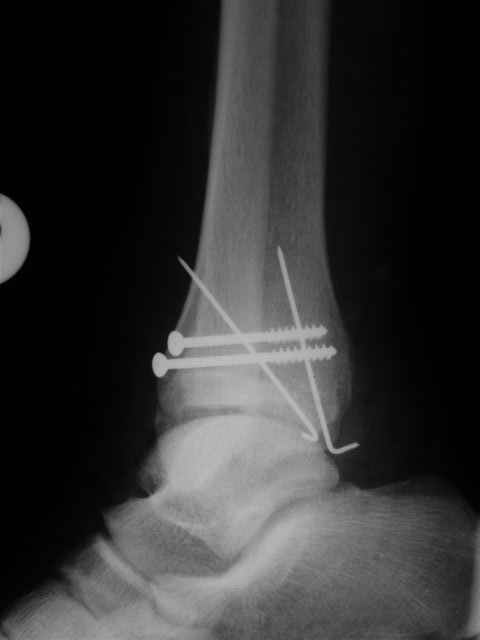

Re: открытый перелом мыщелков бедра, латерального

Я предупреждал, что ничего сверхъестественного. Каюсь, что одна из спиц прошла несколько дальше, чем нужно было, но главное - перелом стабилизирован и больной работает суставом в полном объёме, несмотря на представленную раннее травму коленного сустава.